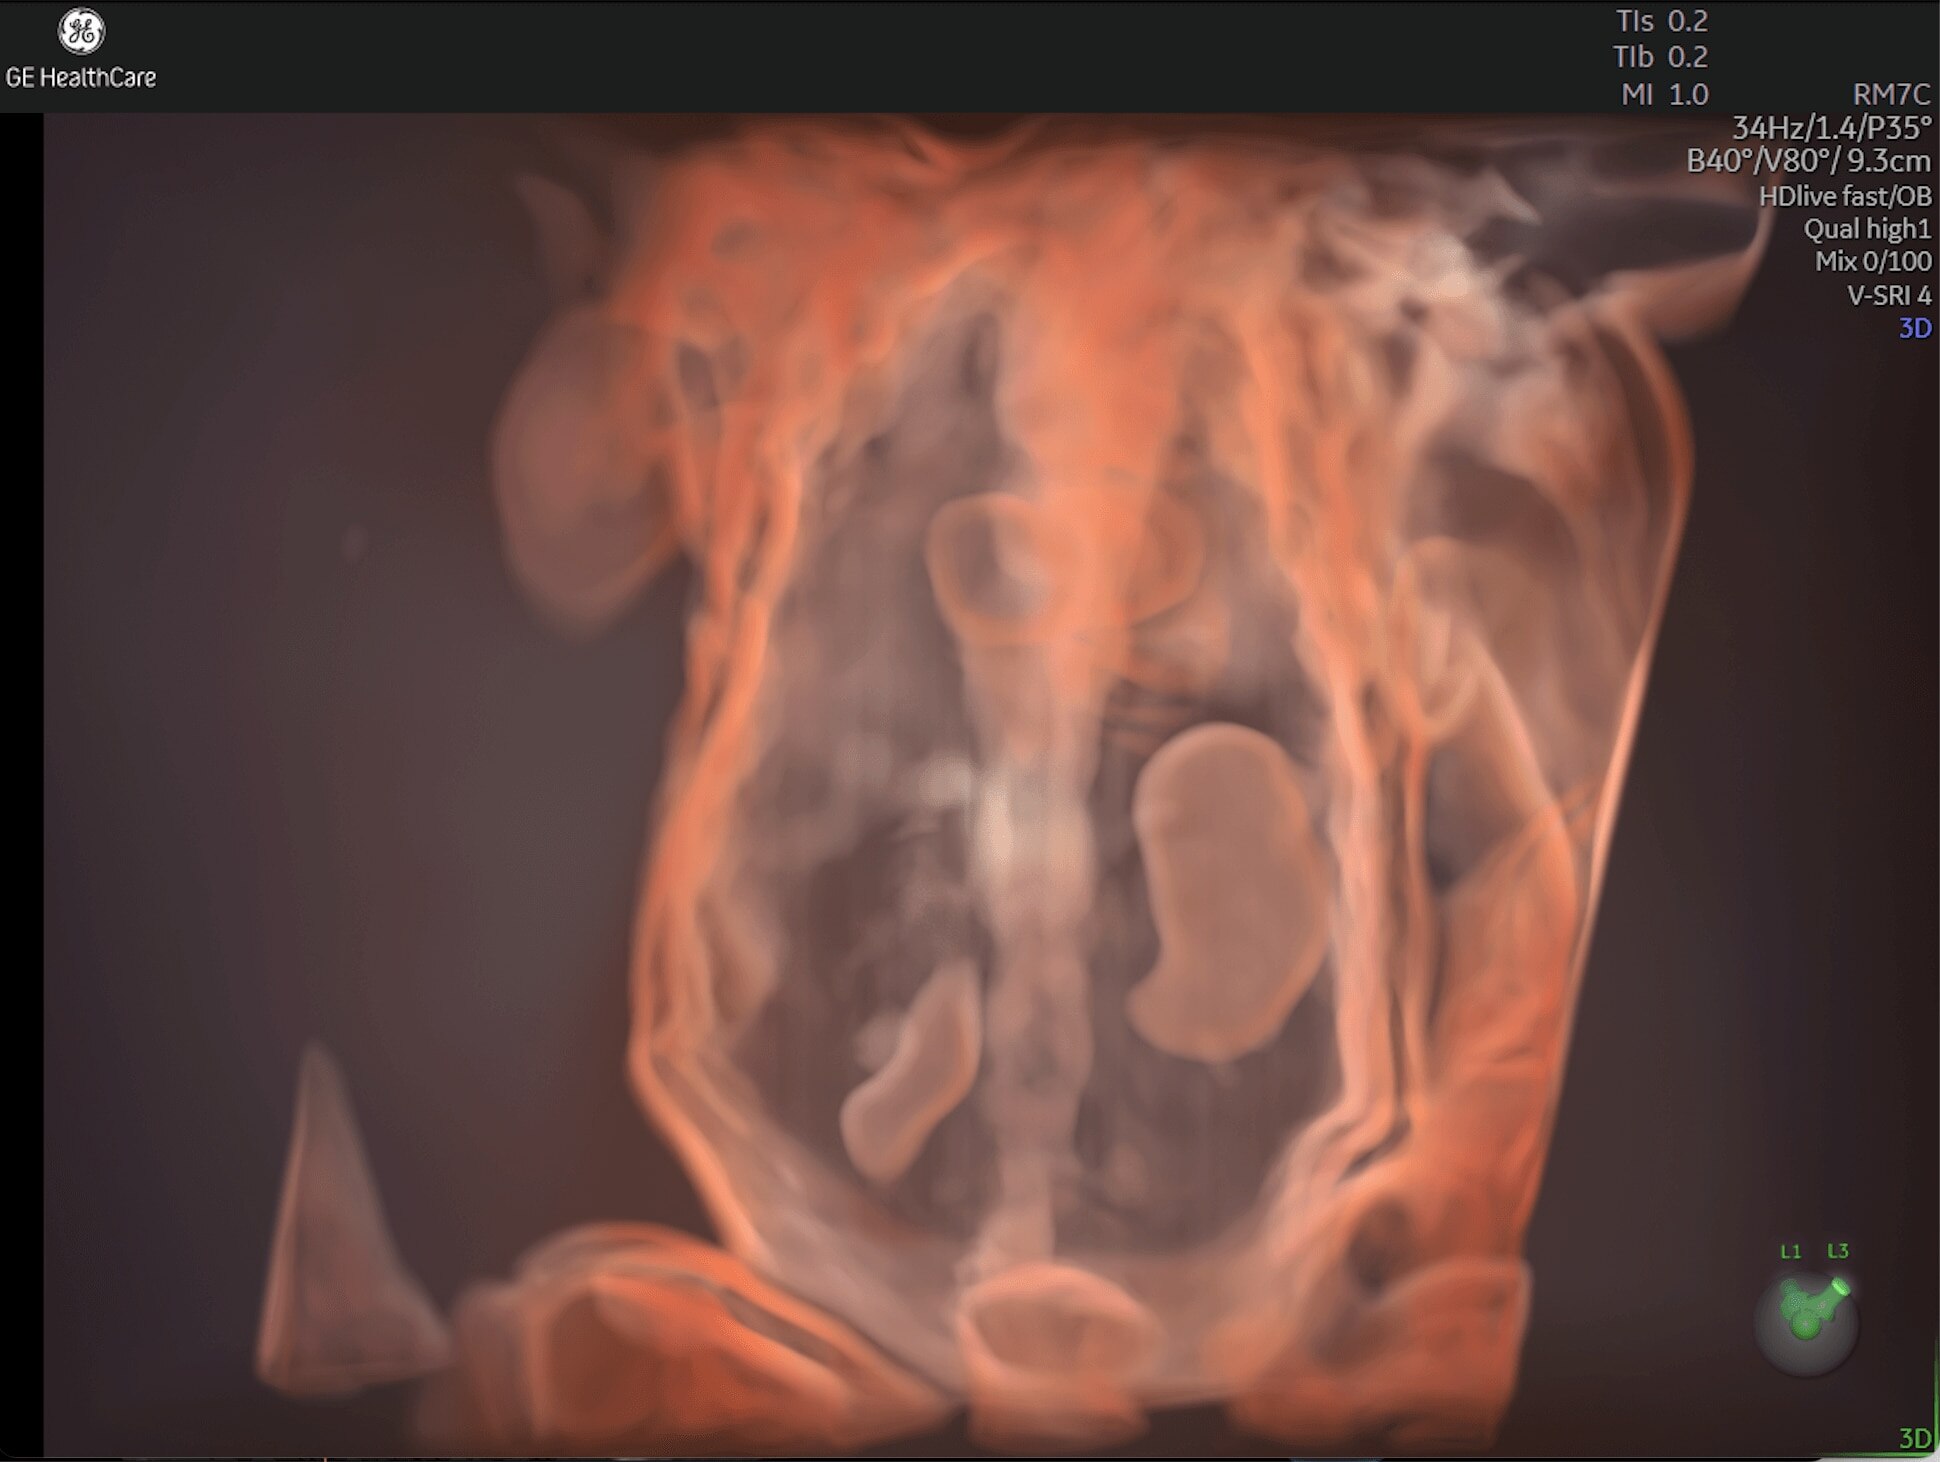

Enhanced Volume Imaging

Deliver next generation 3D/4D & Color images with HDlive Studio+